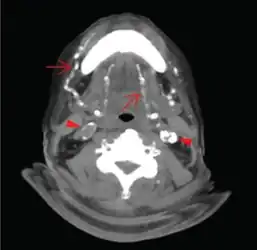

Axial CT slice at the level of C2-C3 soft tissue window setting setting. Extensive calcifications of the bilateral lingual and facial arteries are noted (arrows) as well as calcific plaques at bilateral carotid tree area (arrow heads). -